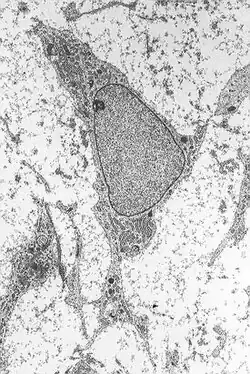

As células mesenquimatosas são células-tronco adultas, pertencentes ao mesênquima, um tecido embrionário. Também estão presentes na pessoa adulta, mas à medida que ele vai envelhecendo, a quantidade destas células no organismo vai diminuindo

Ela se diferencia em muitos tipos diferentes de células, como os fibroblastos, osteoblastos, condrócitos, leucócitos e o mastócito. São importantes na regeneração do tecido.[1][2][3][4]